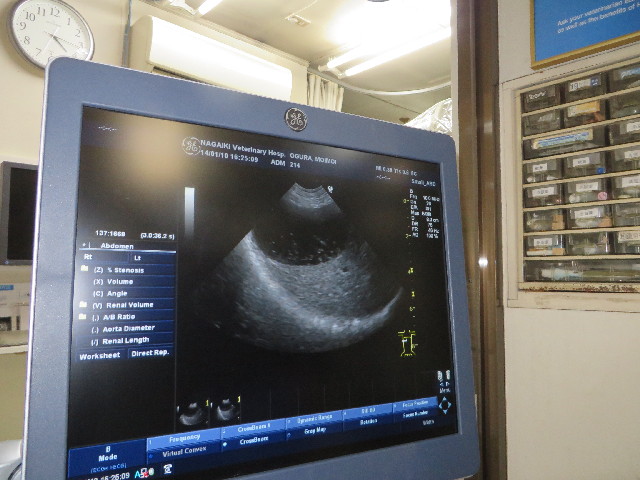

●今日の主診察は月1回のエコー。

胆泥がある(浮いているのがはっきり写っていました。

(このくらいは問題無し)

今はウルソも飲んでいるし、そのうちキレイになるかも。

膀胱は炎症等なくとてもきれい。

肝臓、腎臓など他も問題なし★('-^v)